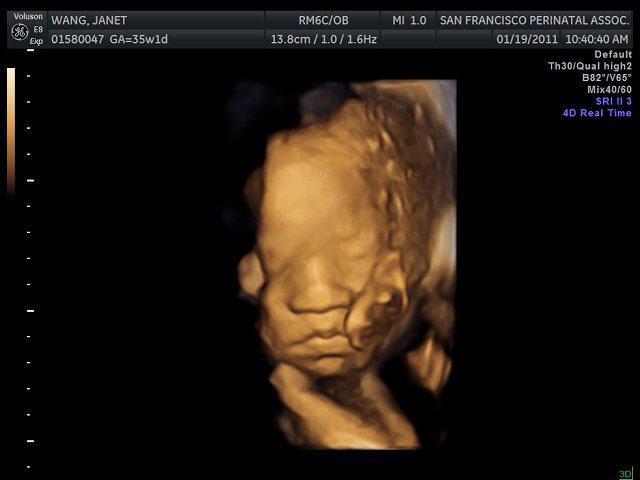

3d images are used to show you three dimensional external images that may be helpful in diagnosing issues such as a cleft lip.

However 4d ultrasound allows us to add live streaming video of the images showing the. Here 3d images are taken and an element of time is added. 4d ultrasound technology is 3d ultrasound in motion. A 4d ultrasound generates an image that is continuously updated much like a moving image.

This allows parents to see their baby in real time. Image the three dimension image or 3d is a still image. 3d scans show still pictures of your baby in three dimensions. 4d ultrasound 3d imaging allows fetal structures and internal anatomy to be visualized as static 3d images.

The most significant difference between 3d and 4d ultrasound is that 4d allows physicians to live stream video of the babys images. 4d scans show moving 3d images of your baby with time being the fourth dimension. 4d ultrasound is essentially 3d ultrasound in live motion. At the same time the depth and detail of 3d and 4d ultrasound imagery is remarkably effective in detecting issues such as a cleft lip heart defects skeletal problems or neural abnormalities.

4d means four dimensional and the fourth dimension is time. A 3d scan will show the facial features such as the ears nose and mouth.